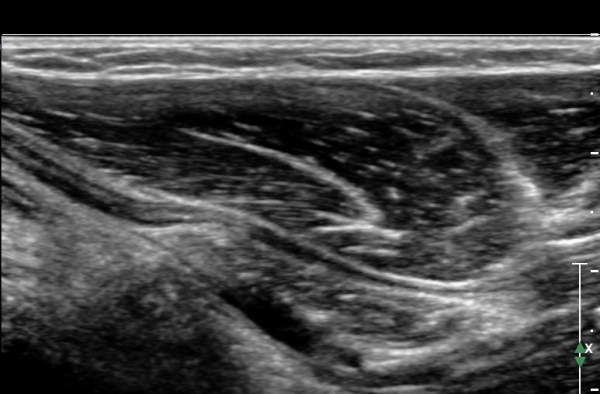

ÃÊÀ½ÆÄ °Ë»ç : ȸ³»±Ù ±ÙÀ§ºÎ¿¡¼ Á¤Á߽Űæ Ⱦ´Ü¸é°Å»ç¿¡¼ ƯÀÌ ¼Ò°ßÀ» º¸ÀÌÁö ¾ÊÀ¸³ª(»çÁø 1) ȸ³»±Ù ¿ä°ñµÎ ±â½ÃºÎ ¿¡¼ Á¤Á߽ŰæÀÇ ±¹°íÀû ¾Ð¹Ú ¹× ÆíÆòȰ¡ °üÂûµÊ(»çÁø 2). ÀÌ·± º¯È´Â °ÇÃø(»çÁø 5)°ú ºñ±³ÇÏ¸é ¶Ñ·ÇÇÔ.

Á¤Á߽Űæ Á¾´Ü¸é°Ë»ç¿¡¼ ȸ³»±Ù ¿ä°ñµÎ ±â½ÃºÎ¿¡¼ Á¤Á߽ŰæÀÇ ±¹¼ÒÀû ¾Ð¹Ú°ú Ç¥ÃþÀ¸·Î ÀüÀ§°¡ °üÂûµÇ°í ¾Ð¹ÚÀÇ ±ÙÀ§ºÎ¿¡¼´Â Á¤Áß½Å°æ ºÎÁ¾ÀÌ °üÂûµÊ(»çÁö 3). ÀÌ·± º¯È´Â °ÇÃø(»çÁø 6)°ú ºñ±³ÇÏ¸ç ¶Ñ·ÇÇÔ.